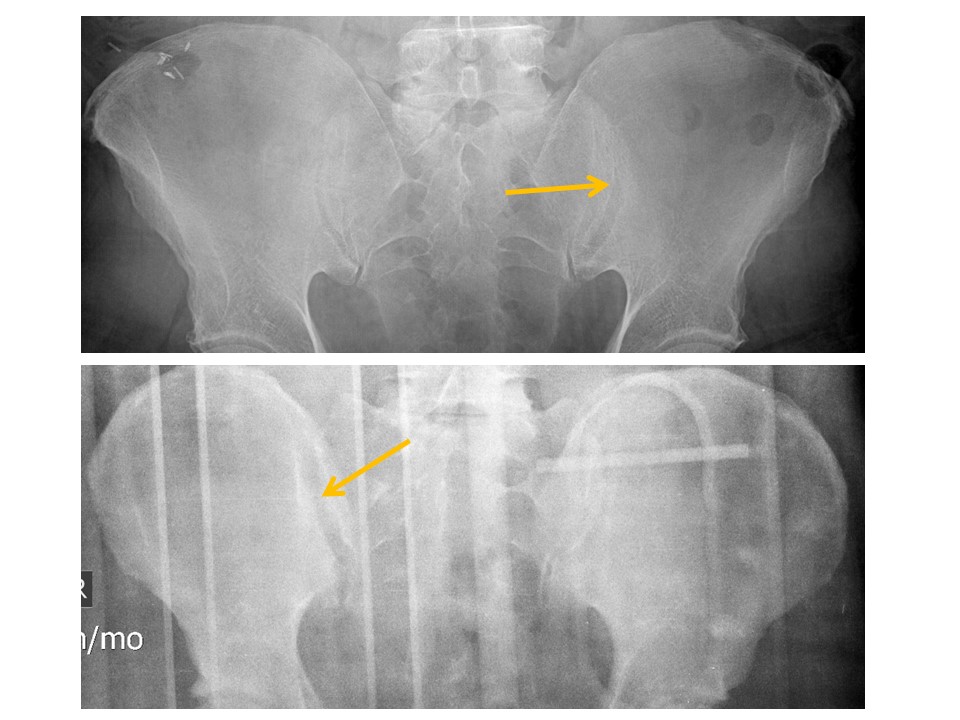

Superior right hip dislocation with fracture of the posterior acetabular wall. A fracture of the femoral head with intra-articular body is also suspected.

CT to further characterize.

Urgent: non-routine communication within 4 hours